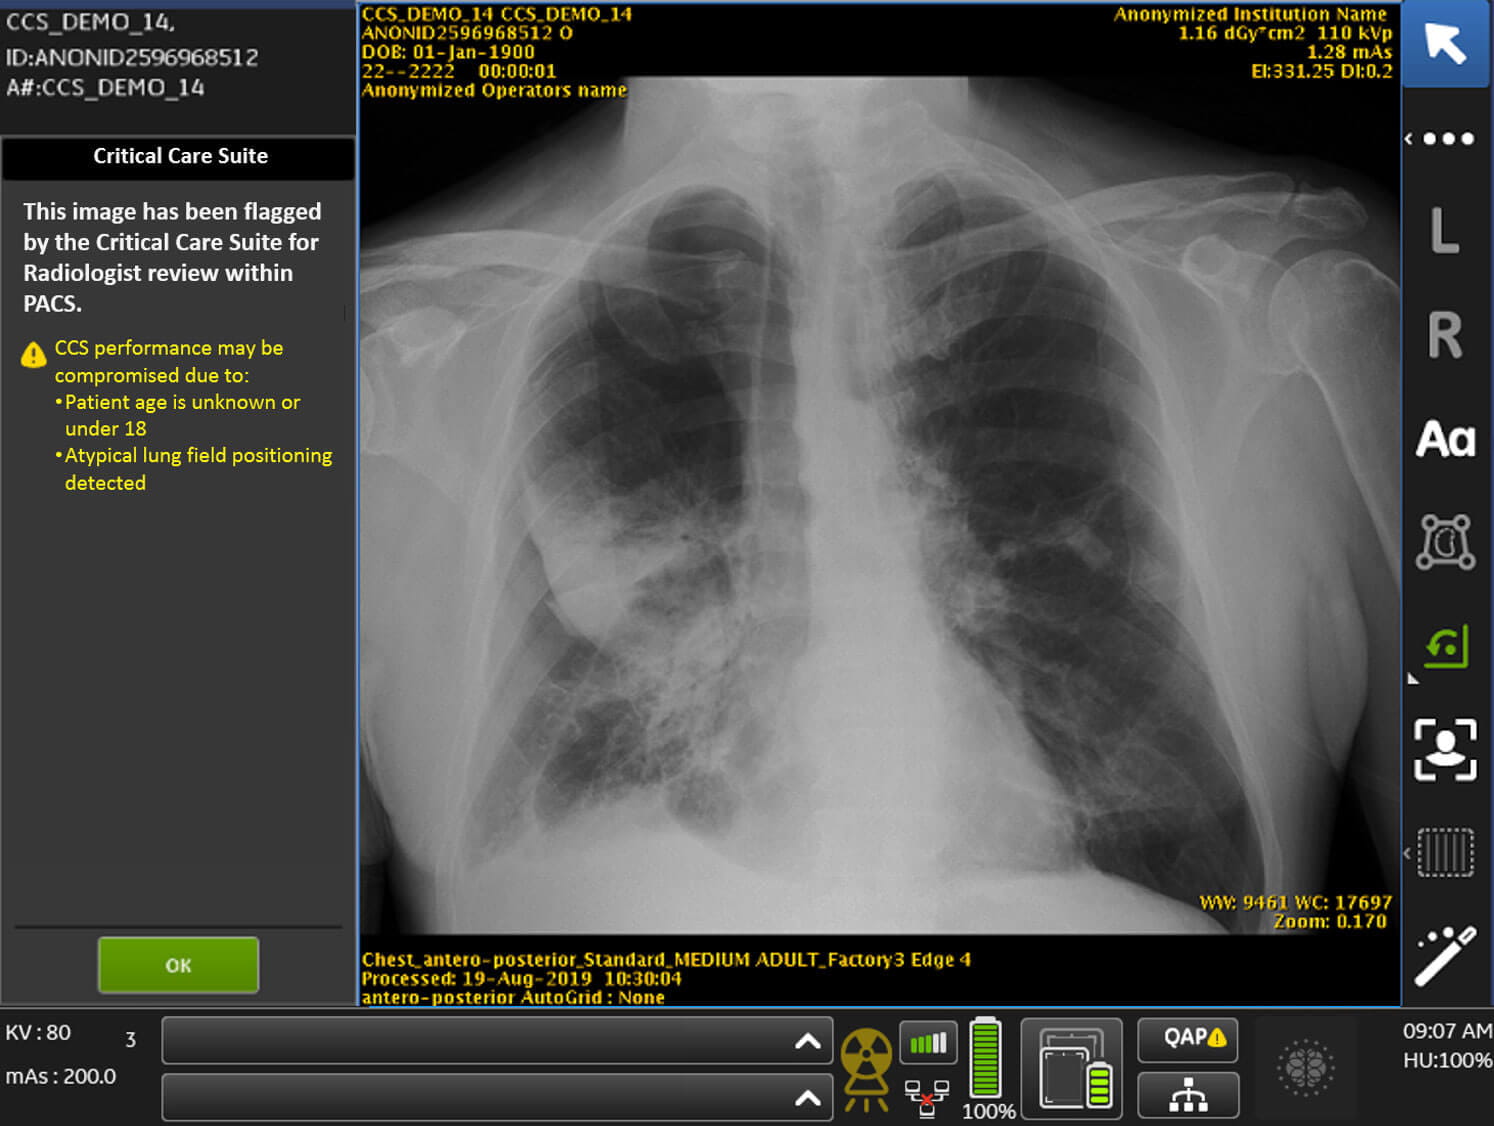

Artificial intelligence identifies collapsed lungs, alerts radiologists

GE Healthcare (GEHC) chose University Hospitals (UH) Cleveland Medical Center in November of 2019 as the first hospital in the US to evaluate its new mobile x-ray system enabled with Critical Care Suite, the world’s first on-device AI solution for triage & notification of critical findings and quality errors. The tool is designed to quickly identify and prioritize cases such as pneumothorax (collapsed lung), which is crucial as ICUs see an increase in patients during the COVID-19 crisis.

Radiologists at UH Cleveland Medical Center read dozens of images every day. This process takes several hours. To assist them, GEHC’s Critical Care Suite software acts as artificial intelligence on board the Optima XR240amx mobile x-ray unit. Once a chest x-ray is taken, it recognizes if a patient has a collapsed lung and flags the image for immediate reading, setting the patient on a rapid path to treatment.

UH evaluated the equipment in the clinical setting, reporting back to GEHC before the company made the system available commercially. UH gauged the sensitivity of the algorithm used to detect critical findings, evaluated workflow and determined the benefit to patients.

Dr. Gupta and Dr. Gilkeson completed the evaluation phase for the Critical Care Suite in December, and the technology is now in daily clinical practice – flagging between 7 to 15 collapsed lungs per day within the hospital. No one on the team could have predicted the onset of the COVID-19 pandemic, but this technology and future research with GEHC may enhance the capability to improve care for COVID-19 patients in the ICU. The Critical Care Suite is now assisting in COVID and non-COVID patient care as the Optima XR240amx travels to intensive care units within the hospital.